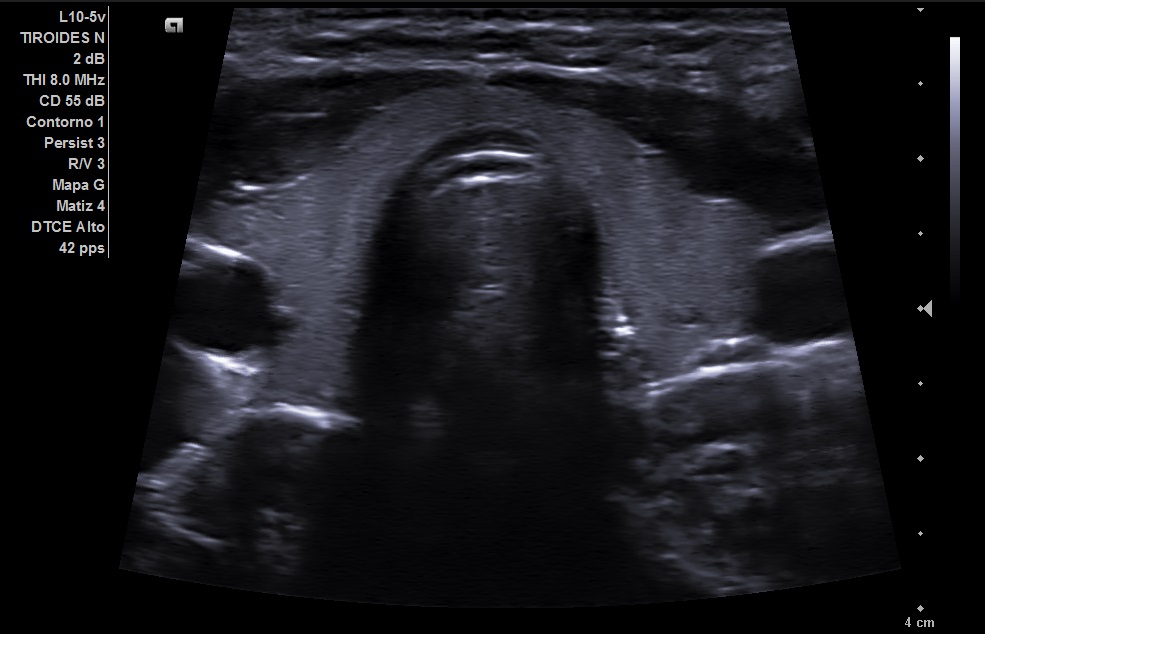

Se realizó en consulta una ecografia clínica, se colocó al paciente decúbito supino con ligera hiperextensión del cuello y tras palpar el bultoma se localizó con la sonda. Visualizamos en nivel 1 una imagen hipoecogénica ovalada de 22 mm con alteración de la estructura pero con hilio graso conservado y con aumento de vascularización compatible con adenopatía reactiva.